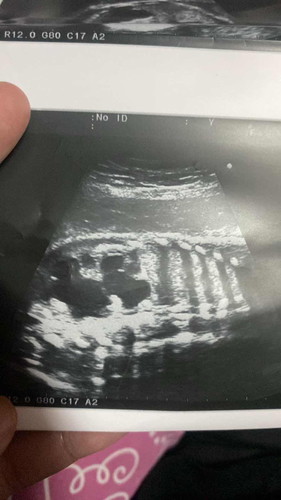

สอบถามแม่ๆหน่อยได้ไหมคะ พอดีตอนนี้หนูท้องได้33 w แล้วเมื่อวานได้ไปซาวด์มาคุณหมอบอกว่า พบจุดดำๆช่วงลำไส้น้อง หมอไม่แน่ใจว่าเป็นแก๊สหรือลำไส้อุดตัน มีแม่ๆคนไหนเคยพบบ้างมั้ยคะ ตอนนี้หนูกังวลกลัวลูกเป็นอันตรายค่ะ 😔

VIP Parentsสอบถามแม่ๆหน่อยได้ไหมคะ พอดีตอนนี้หนูท้องได้33 w แล้วเมื่อวานได้ไปซาวด์มาคุณหมอบอกว่า พบจุดดำๆช่วงลำไส้น้อง หมอไม่แน่ใจว่าเป็นแก๊สหรือลำไส้อุดตัน มีแม่ๆคนไหนเคยพบบ้างมั้ยคะ ตอนนี้หนูกังวลกลัวลูกเป็นอันตรายค่ะ 😔